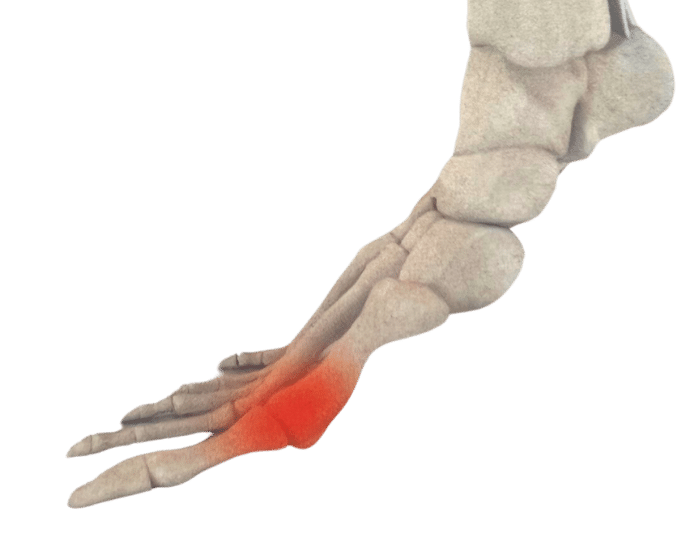

There are numerous reasons why you might need Custom Foot Orthotics. If you have pain in your foot, heel, knee or hip, have high arches or flat feet; or just being regularly on your feet and are getting any aches or pains in the feet or legs, or suffering from general foot pain while walking, running, playing sports or even at rest you qualify for Custom Foot Orthotics.